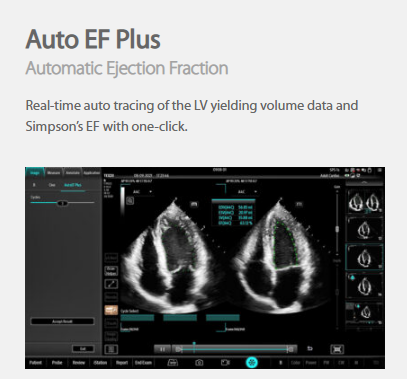

The technology-rich TE X Ultrasound System gives clinicians access to market-leading artificial intelligence (AI)-powered Smart Tools, an ergonomically designed system, and proprietary software-based beamformer Zone Sonography Technology+ (ZST+). By incorporating these elements, the TE X Ultrasound System provides access to advanced diagnostic data, the ability to adapt to the various clinical scenarios at point of care, and best-in-class imaging to help them provide a higher standard of care.